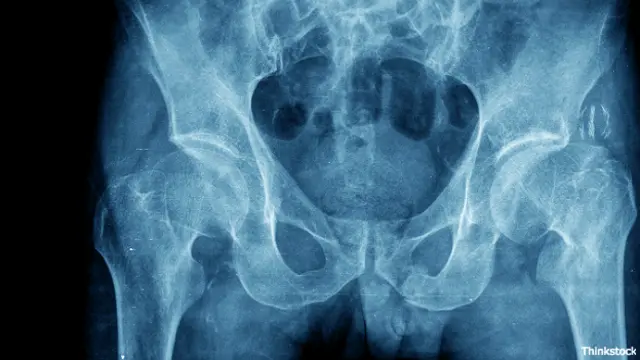

Place de huesos de la cadera

Pie de foto, Cada año en México se registran 75.000 fracturas óseas por osteoporosis.

Cada año en el país se registran 75.000 fracturas óseas por osteoporosis y la investigadora ya trabaja en el próximo paso: ensayos en humanos.